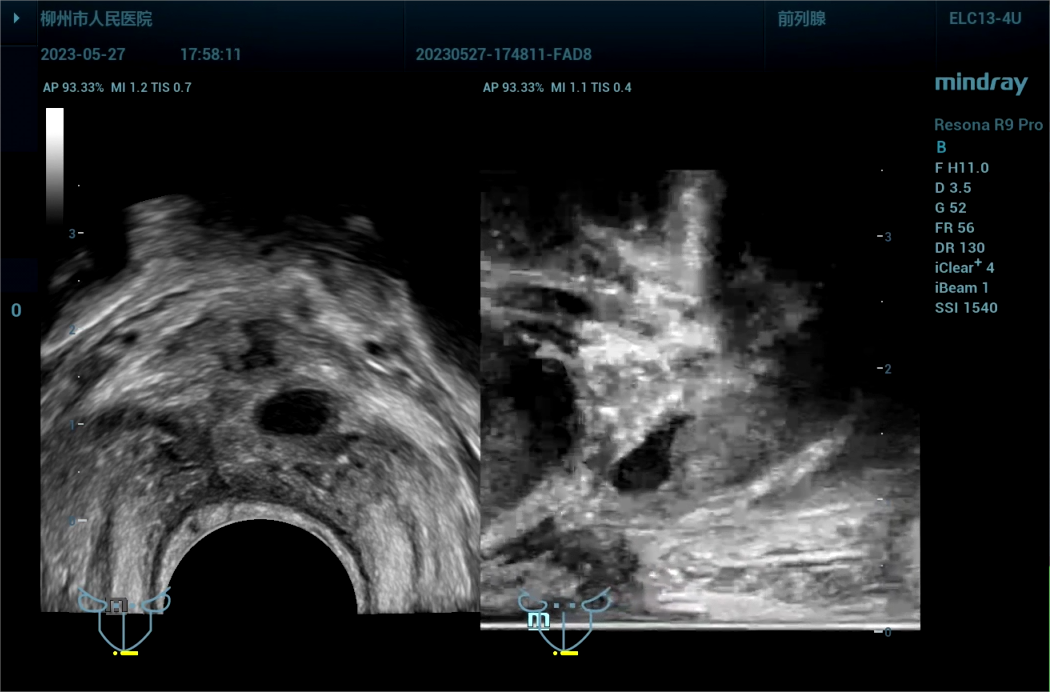

病史为,30岁年轻男性,主诉为反复尿痛2年余。临床诊断是尿路感染。

443081 截取视频 截取视频 截取视[00_23_49][20230614-071701].png